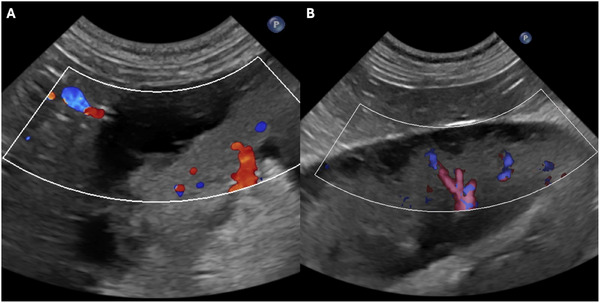

A 9-year-old male neutered Labrador Retriever was referred for azotemia and bilateral renomegaly. An abdominal ultrasound revealed severe bilateral renomegaly with septated subcapsular cystic anechoic lesions, consistent with renal lymphangiectasia. Despite conservative management, the patient died. Necropsy and histopathology confirmed dilated subcapsular vascular structures. Renal lymphangiectasia is a rare, benign dilation of renal lymphatics previously reported in human medicine. This case represents the first description of sonographic features of renal lymphangiectasia in a canine patient.

一只9岁的拉布拉多雄性绝育猎犬因氮血症和双侧肾肿大而被转诊。腹部超声显示严重双侧肾肿大伴囊下分离性囊性无回声病变,符合肾淋巴管扩张。尽管进行了保守治疗,患者还是死亡了。尸检和组织病理学证实包膜下血管结构扩张。肾淋巴管扩张是一种罕见的,良性扩张的肾淋巴管先前报道在人类医学。本病例首次描述犬患者肾淋巴管扩张的声像图特征。